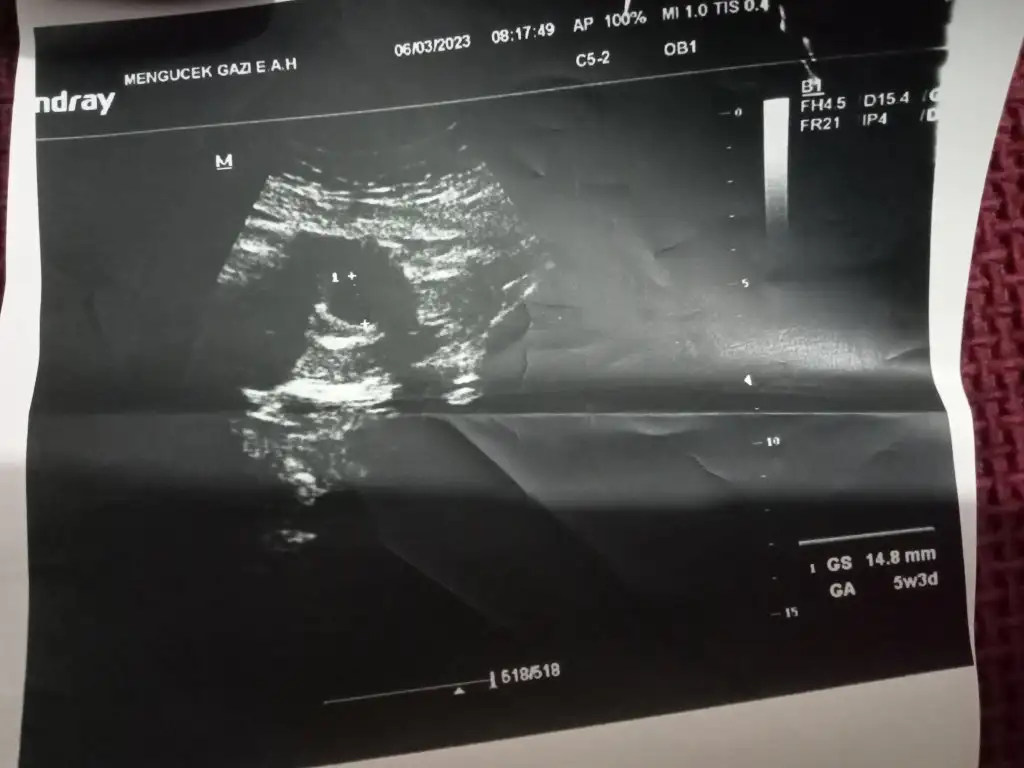

Sizce boşmudur kese varmı bebek ilk ki düşük olduğu için çok pinpirikliyim